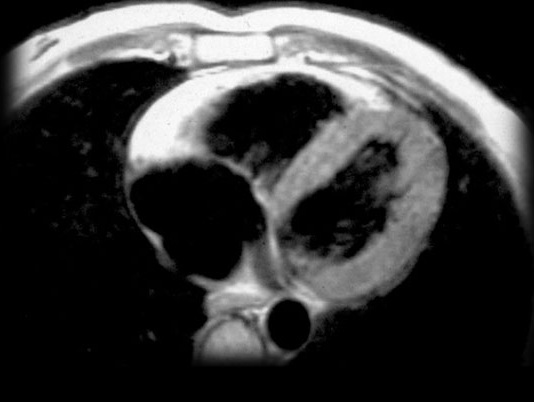

ARVC以右心室的脂肪浸润为主要特征(如下图所示),从而导致RV肥大,可能导致致命的心律失常。在兰尼碱钙通道受体异常也有报道。

ARVC多见于意大利北部威尼托地区居民(及其后代),被认为是常染色体显性遗传。这种疾病的初期表现为心源性猝死;因此,筛查患者的家庭成员是确诊新病例的关键。